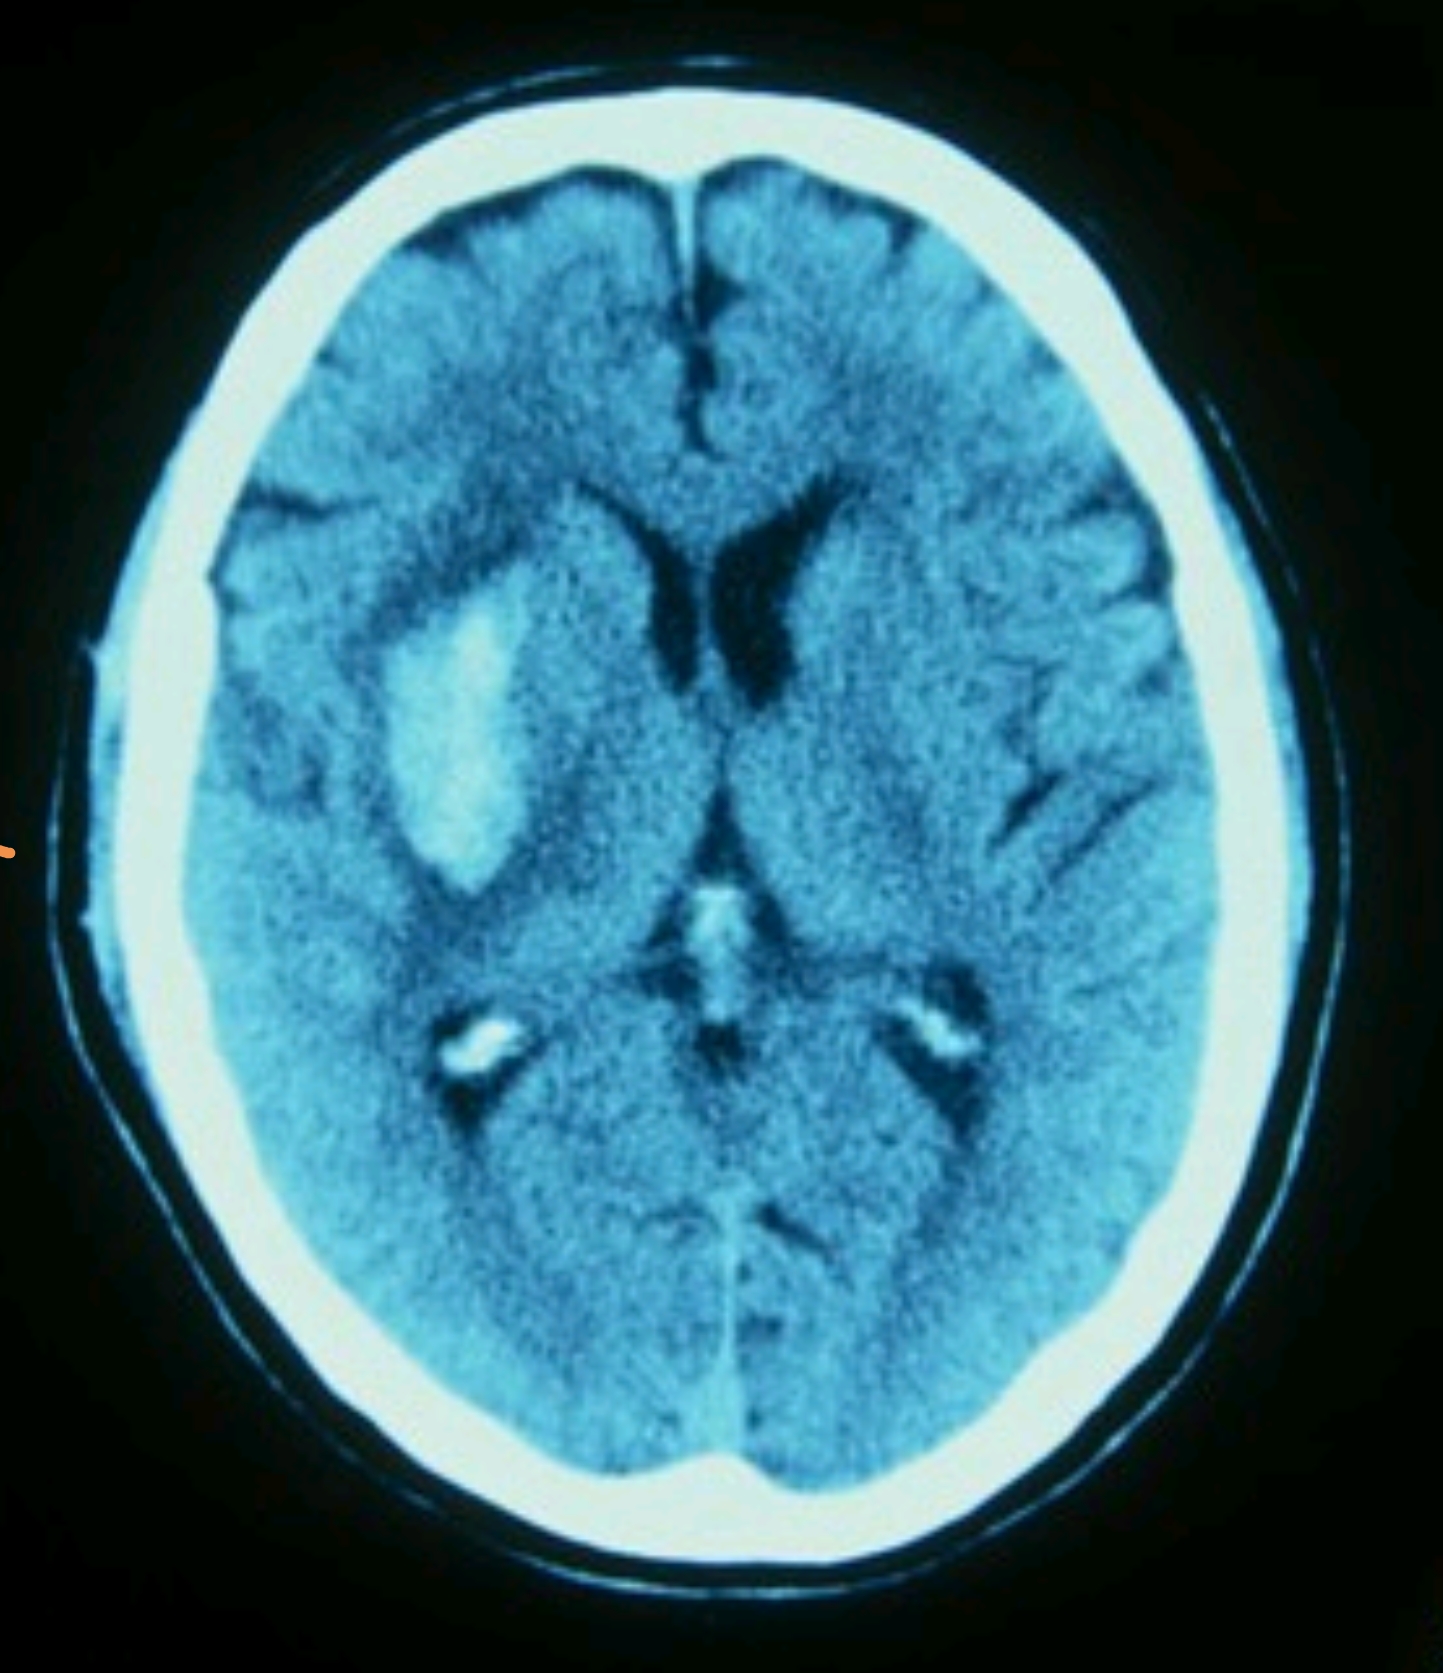

颅脑CT主要用于诊断脑部相关疾病脑出血可清晰显示出血部位范围及血肿形态,辅助判断出血量及病情严重程度脑梗塞通过观察脑组织密度变化,早期发现缺血性病灶,为溶栓治疗提供依据其他系统疾病如颅内肿瘤脑外伤脑积水等,可评估病变位置大小及与周围组织的关系肺部CT是呼吸系统疾病的;脑肿瘤患者CT检查可以发现脑部肿瘤的位置大小和形态,对于肿瘤的诊断和治疗方案制定具有重要意义血管异常患者CT检查能够显示脑部血管的异常,如动脉瘤血管狭窄等,有助于预防和治疗脑血管疾病脑萎缩患者通过CT检查可以观察脑组织的萎缩程度,为评估病情和制定治疗方案提供参考结节性硬化患者CT;脑CT能够检查出多种脑部疾病,主要包括以下几类1 外伤性疾病脑CT是诊断急性颅脑外伤的首选影像学方法可清晰显示脑出血包括硬膜外血肿硬膜下血肿脑内血肿脑挫裂伤颅骨骨折及颅内积气等例如,硬膜外血肿通常表现为双凸镜形高密度影,而脑挫裂伤则表现为局部脑组织低密度区伴点状出血;神经功能缺损症状若患者出现头晕耳鸣呕吐口齿不清肢体无力或感觉异常等神经功能缺损症状,需尽快进行头部CT检查这类症状可能由脑梗塞脑出血或颅内肿瘤等疾病引起,CT可快速鉴别病变性质如缺血性或出血性例如,突发口齿不清可能是脑干梗塞的征兆,CT检查能尽早明确诊断并启动溶栓或取栓;当患者出现以下情况时,需要做脑部CT检查出现神经系统症状肢体活动不利如手脚无力行动不便等语言笨拙说话不清楚表达困难等饮水呛咳在饮水时出现呛咳现象头痛头晕持续或突发的头痛眩晕感怀疑脑血管疾病脑部出血通过CT检查可以迅速判断是否存在脑出血脑部肿瘤CT检查有助于;脑部结构异常如腔隙灶,即微小的脑组织缺血坏死灶,可通过脑部CT检测到还可检测到脑萎缩脑积水等脑部结构异常脑血管畸形如动静脉畸形烟雾病等,这些疾病可能导致脑出血或脑缺血,通过CT检查及相关增强特殊CT检查可明确诊断综上所述,脑部CT检查是一种重要的医学影像检查手段,能够诊断多种;CT能检查出脑血栓,但诊断并非绝对特异CT通过X射线扫描脑部组织,可显示脑血栓的典型影像学特征,主要包括以下几种表现低密度梗死灶脑血栓导致局部脑组织缺血坏死后,CT图像上会呈现与正常脑组织密度不同的低密度区域,这是最常见的直接征象混杂密度梗死灶若梗死灶内发生出血性转化如血性脑。

脑CT能查出以下疾病颅内肿瘤包括良性和恶性肿瘤,如胶质瘤脑膜瘤垂体瘤等颅内炎症如脑炎脑膜炎等,可显示脑组织的炎症改变和水肿情况颅内结核可显示结核病灶及其引起的脑组织改变代谢性疾病如脑白质营养不良脑钙化等,可显示脑组织的代谢异常遗传性疾病如神经纤维瘤病结节;CT脑部检查可诊断多种脑部疾病,具体如下1 脑血管疾病CT检查能快速显示脑部血管状况,诊断脑出血脑梗死蛛网膜下腔出血等疾病通过影像可明确血管破裂或堵塞的位置及范围,为急性期治疗提供关键依据例如,脑出血在CT上表现为高密度影,而脑梗死则呈现低密度区域2 脑部肿瘤CT可发现脑部原发;2 脑部退行性疾病脑CT可辅助诊断阿尔茨海默病帕金森病等神经退行性疾病阿尔茨海默病CT可见脑萎缩如海马体缩小及脑室扩大,但早期诊断需结合MRI或生物标志物帕金森病CT可显示中脑黑质多巴胺能神经元减少及路易小体相关改变,但MRI或功能影像更敏感3 脑部炎症脑CT可检测脑炎脑膜炎等;肝脏专项病变除上述腹部检查外,CT对肝脏病变的检出尤为敏感可发现肝硬化肝脏形态改变脂肪肝密度降低肝脓肿环形强化灶及肝血管瘤典型“快进慢出”强化表现等,为临床治疗提供关键依据CT通过断层成像技术,能精准显示人体内部结构,为多种疾病的早期诊断治疗方案制定及预后评估;脑CT检查能查出以下主要疾病脑部出血脑CT对急性脑出血高度敏感,可快速显示血肿位置大小及出血量,帮助判断出血严重程度,是急诊诊断脑出血的首选方法脑部梗死通过观察脑组织密度变化,脑CT可发现脑梗死灶,确定梗死范围及部位,尤其对发病24小时内的超急性期梗死有一定诊断价值脑部肿瘤脑CT能。